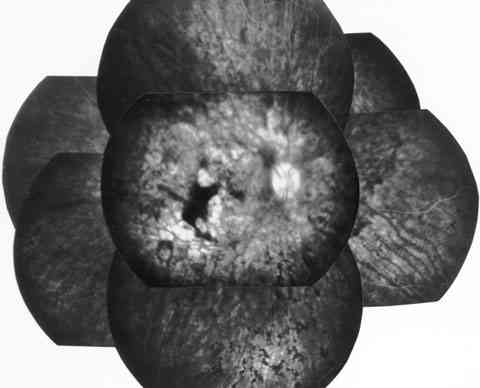

Figura 6

f07-06.jpg (30652 bytes)